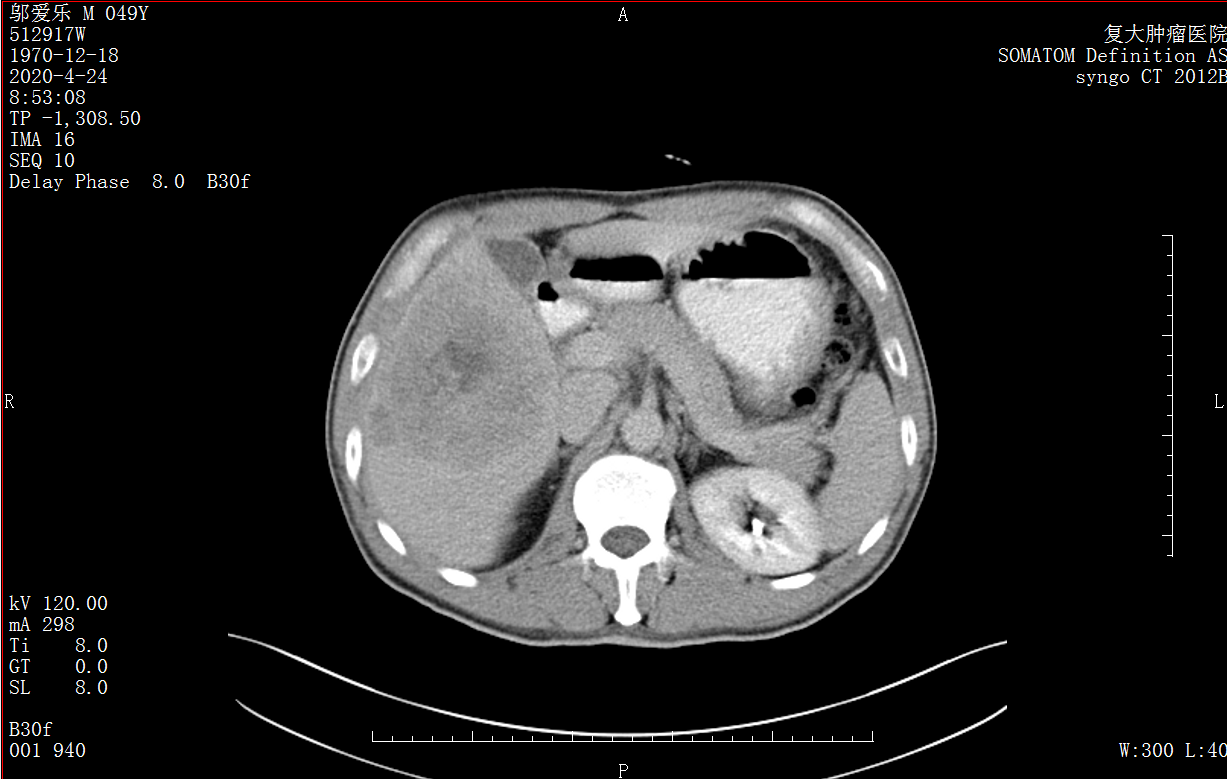

Снимок КТ печени до операции